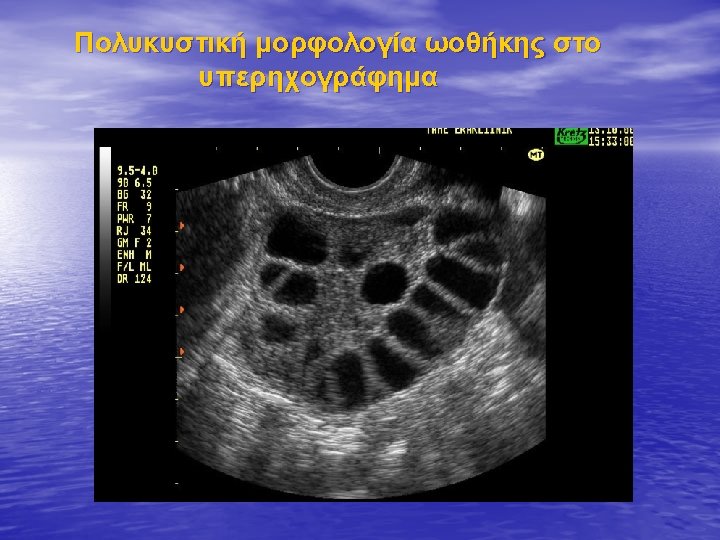

Unravelling the phenotypic map of polycystic ovary syndrome (PCOS): a prospective study of 634 women with PCOS. Evanthia Diamanti-Kandarakis and Dimitrios Panidis • Results. Classic PCOS phenotype was more frequent (85· 96%) than the non-classic phenotype (14· 04%). The patients were also classified according to the presence of biochemical (80· 60%) or clinical hyperandrogenaemia (12· 62%), and, in the newly introduced group, to absence of evidence of hyperandrogenaemia (6· 78%). Subjects with classic PCOS with biochemical hyperandrogenaemia (74· 76%) were more insulin resistant than controls. In women with PCOS, follicle number was positively related to both insulin resistance and biochemical hyperandrogenaemia. Additionally, women with PCOS had a 6· 58 -fold increased relative risk (RR) of > 12 follicles on intravaginal ultrasound a 2· 94 -fold increased RR of ovarian volume > 10 cm 3 compared to controls. • Conclusion. The most frequent PCOS phenotype is the subgroup with biochemical hyperandrogenaemia only within the classic phenotype, which is more insulin resistant than the control group. The follicle number, a newly introduced ultrasonographic marker, is related to both metabolic and hormonal features of PCOS.